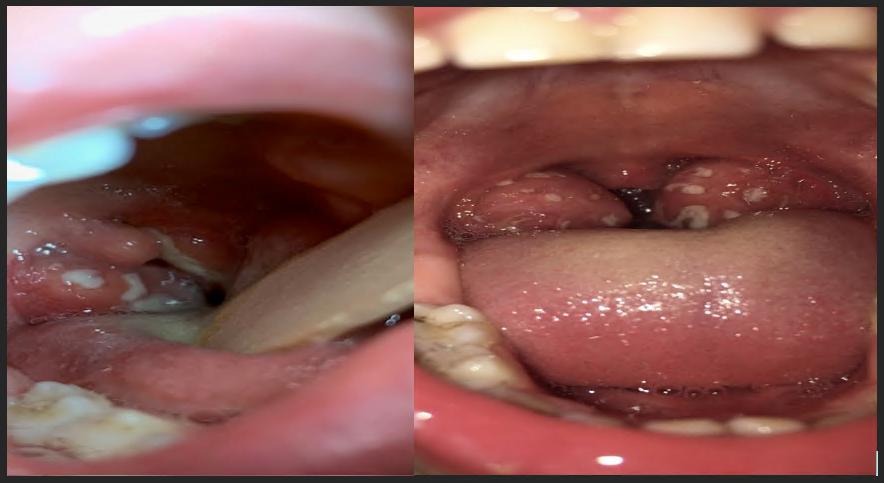

Bu durumda ilk olarak “yineleyen kriptik tonsillit” olasılığını ekarte etmek gerekiyor, bunun da tek yolu dikkatli bir biçimde ve ateşin ikinci günü bademcik muayenesinin yapılmasıdır. Bu hastalık ek olarak ağızda aft ile beraber olursa PFAPA olarak değerlendirilir. Sonuçta yılda 6 defadan veya 6 ayda 3 defadan fazla atak olursa bademciklerin alınması gerekir. (kriptik tonsillit resimleri aşağıda)